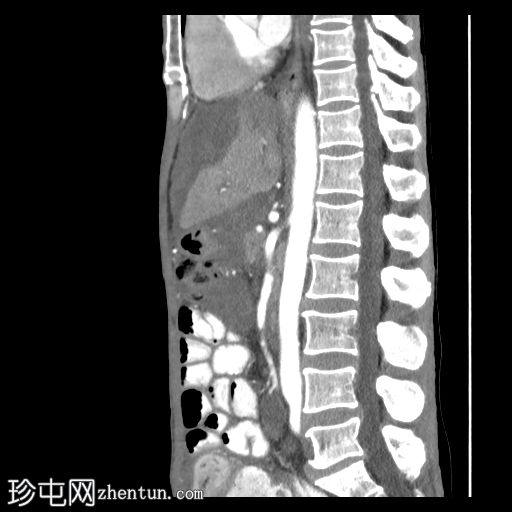

矢状位增强扫描(动脉期)

大网膜和肠系膜内可见低密度、不均匀的腹膜积液,脏器表面呈扇形凹陷,尤其以肝脏和脾脏最为明显。

阑尾肿大,长 5.0 cm,直径 1.2 cm,大小符合,可能提示阑尾黏液性肿瘤

可见双侧少量胸腔积液(右侧:1.0 cm;左侧:0.2 cm),右下后基底段被动性塌陷。